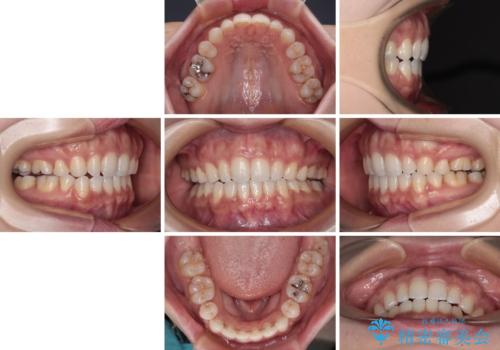

唇が閉じにくい ワイヤー装置での抜歯矯正

- 唇が閉じにくく、上の前歯が下唇に当たって気になるとのことで来院された患者様です。

レントゲン写真での分析結果からは、抜歯矯正をするかどうか悩む境界線上でしたが、主訴が口元の突出感であったため、上下左右の第一小臼歯4本を抜歯して矯正治療を行うこととしました。

上下ともに前歯が少し舌側に傾斜したような仕上がりとなりましたが、口が閉じやすくなったとのことで、患者様には大変満足していただけました。